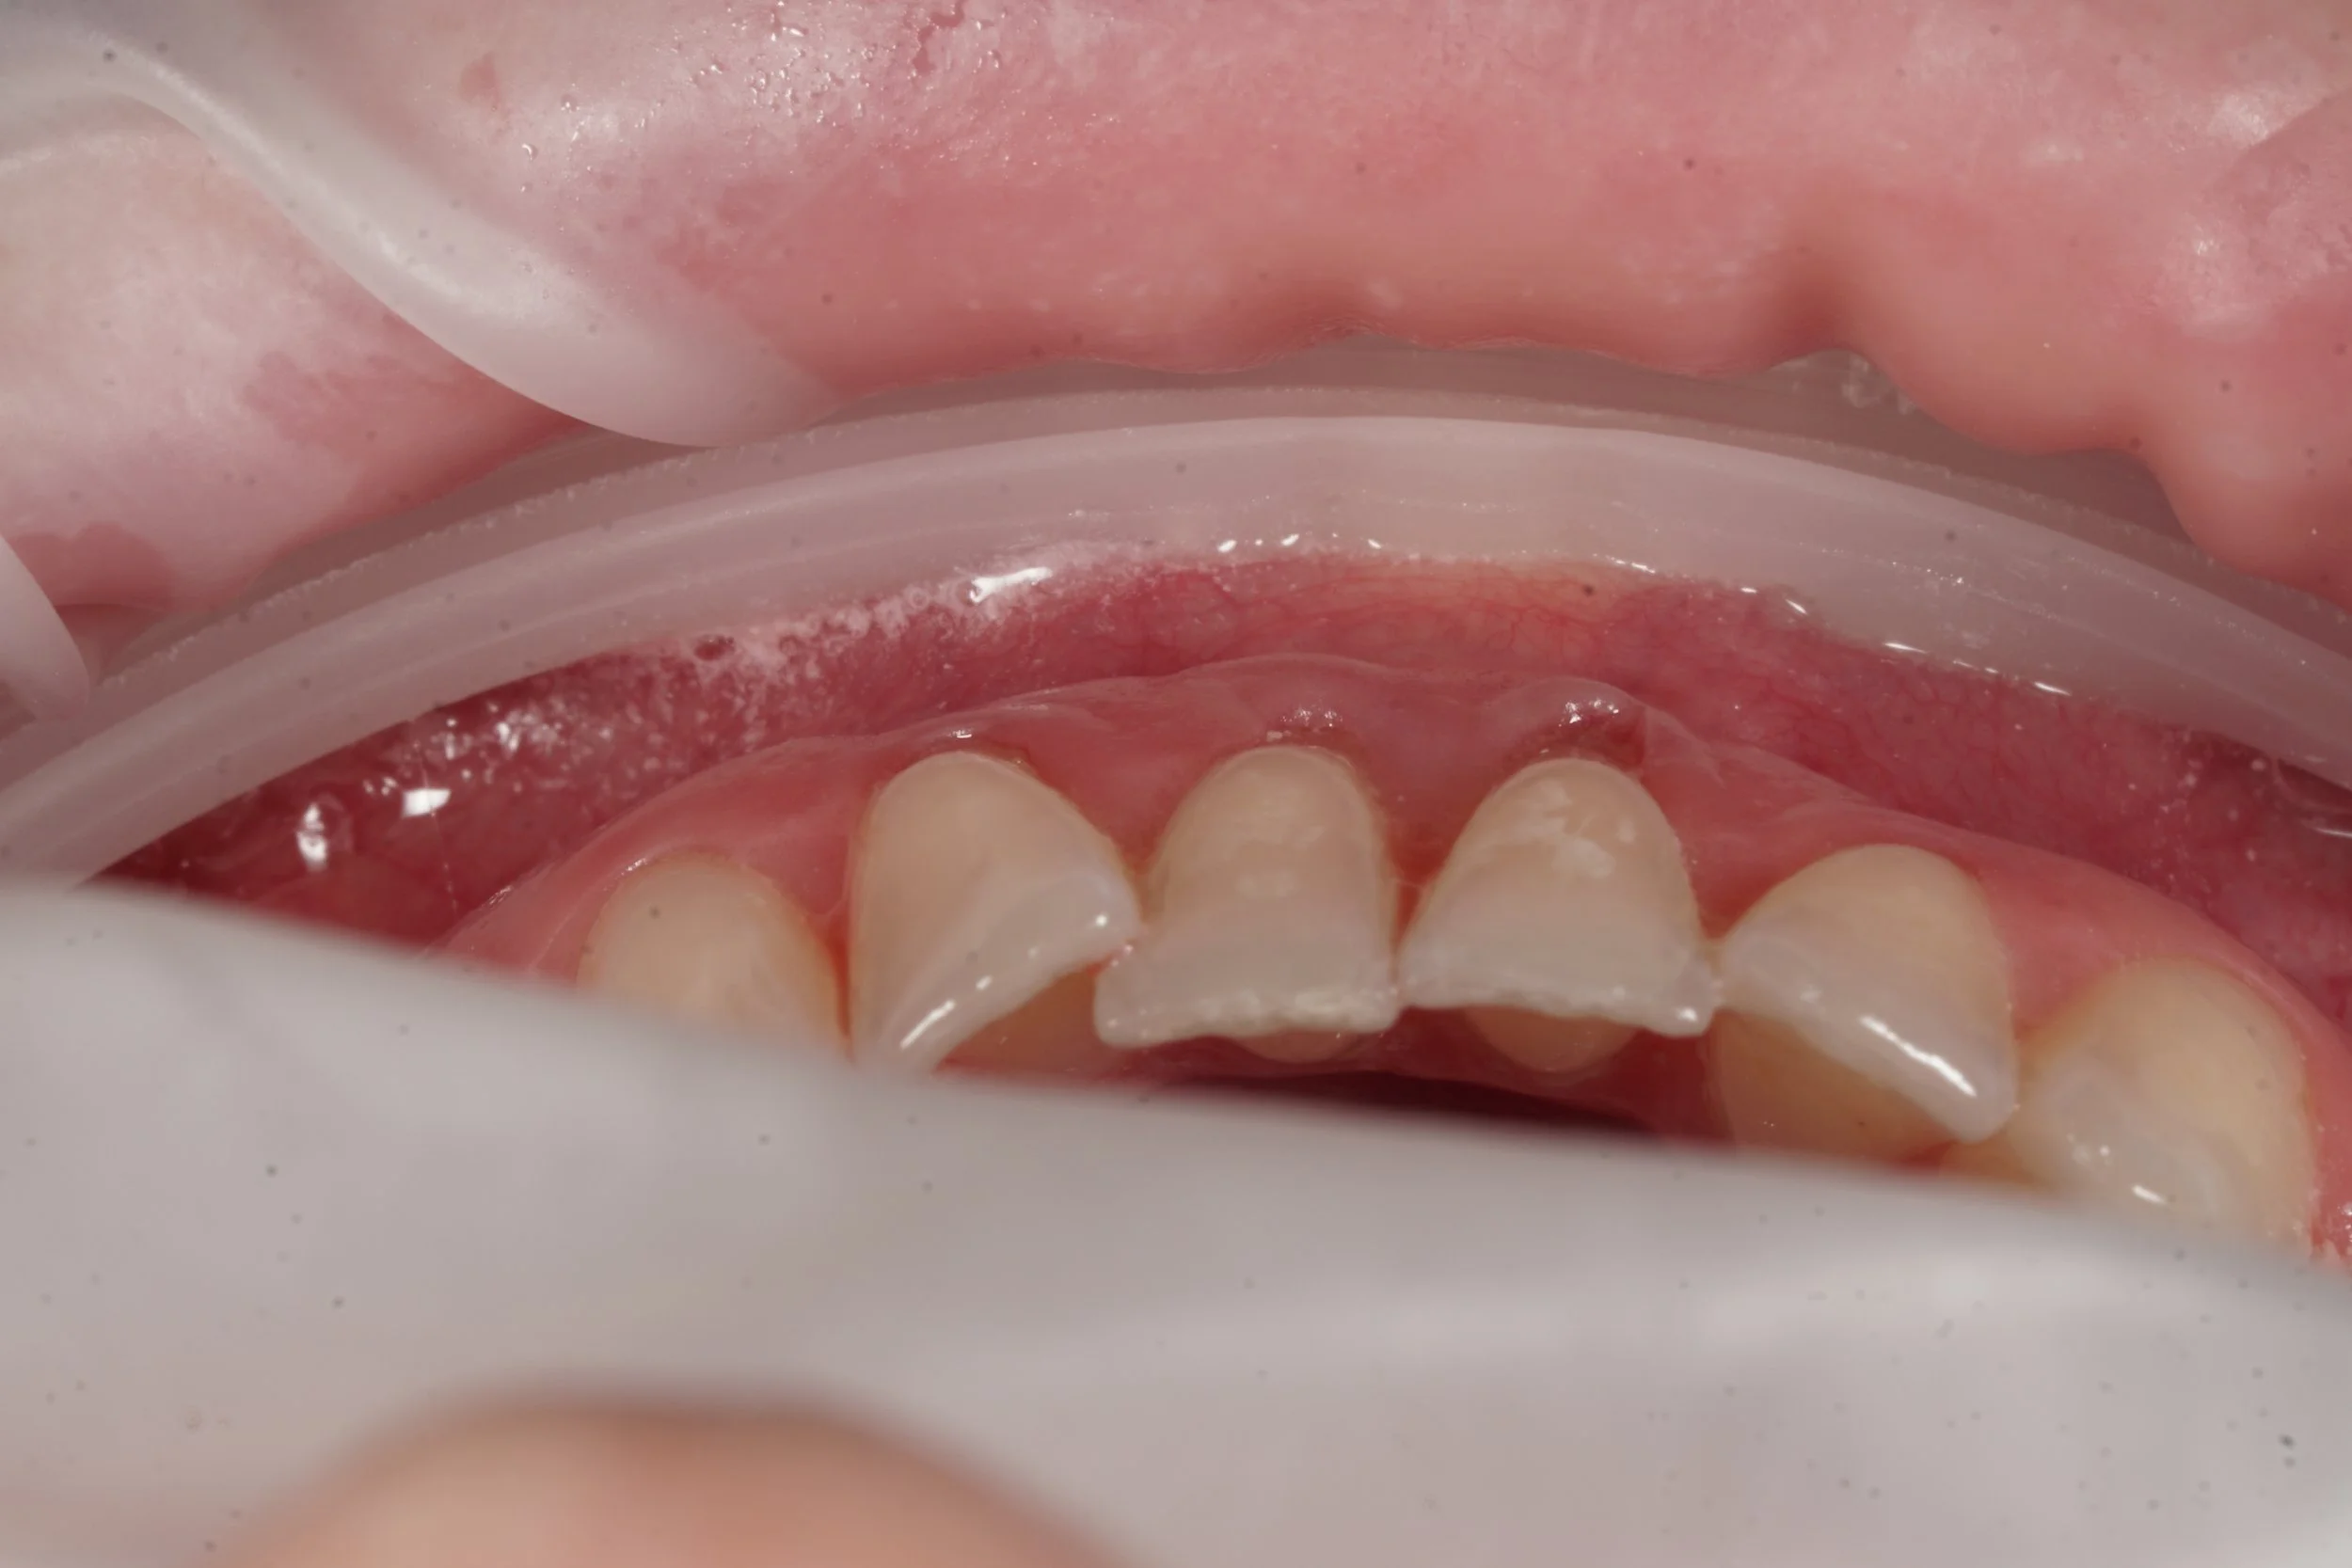

A composite filling done to treat the defect followed by a minimally invasive tunnelling technique for gum grafting

After

2 week after minimally invasive tunnel approach for gum grafting, connective tissue graft

2 weeks after surgery